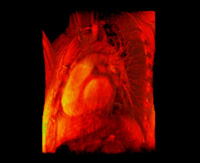

- Beating heart, 256x256x32, 1D transfer, slice rendering

- Beating heart, 256x256x32, 1D transfer, raycasting